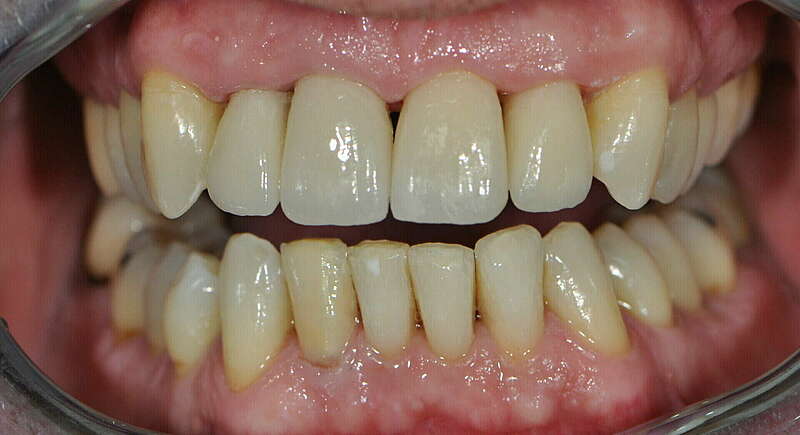

1. Restauration complète maxillaire et mandibulaire